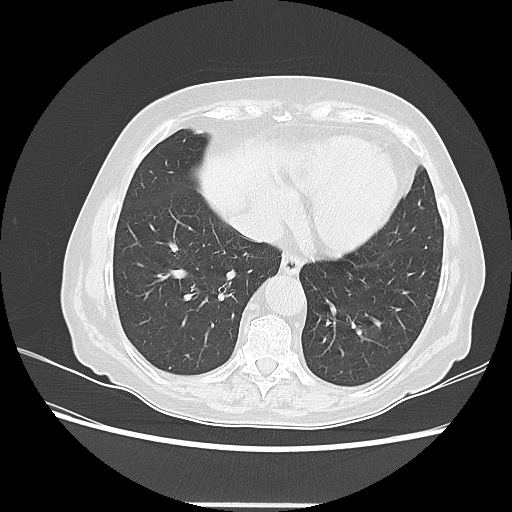

Reconstructed NATIVE CT scan (cycle consistency)

Full window (WL 1023.5, WW 4095 β†’ Low βˆ’1024, High +3071)

Lung window (WL -600, WW 1500 β†’ Low βˆ’1350, High +150)

Mediastinum window (WL 40, WW 400 β†’ Low βˆ’160, High +240)